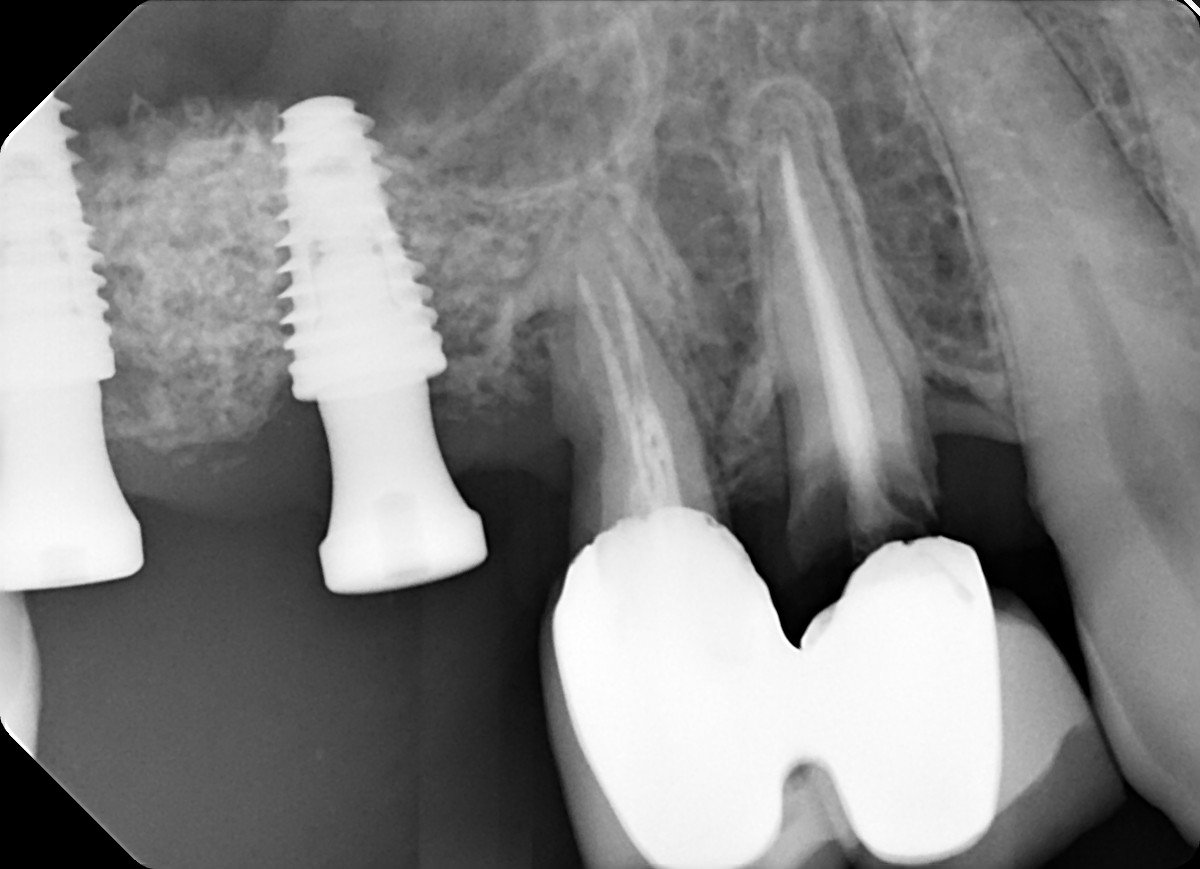

11. What option can be selected for root canal treatment of the tooth #3.6?

12. What option can be selected for root canal treatment of the tooth #3.7?